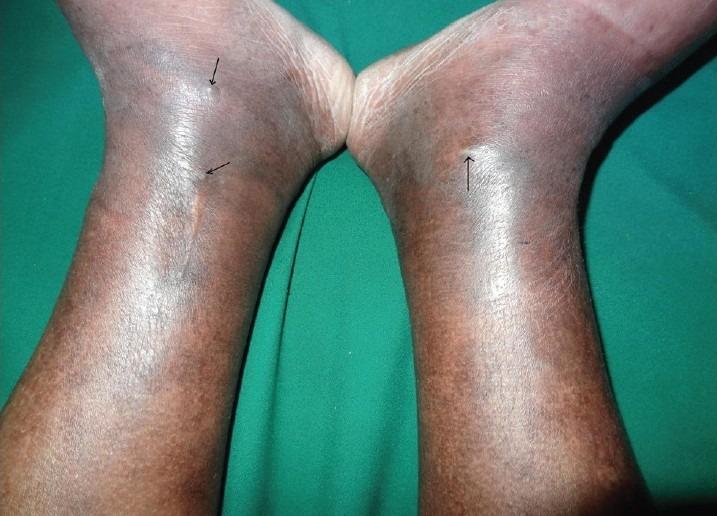

Venous ulcers are the most common ulcers of the lower limb. It has a high morbidity and results in economic strain both at a personal and at a state level. Chronic venous hypertension either due to primary or secondary venous disease with perforator paucity, destruction or incompetence resulting in reflux is the underlying pathology, but inflammatory reactions mediated through leucocytes, platelet adhesion, formation of pericapillary fibrin cuff, growth factors and macromolecules trapped in tissue result in tissue hypoxia, cell death and ulceration. Duplex scan with colour flow is the most useful investigation for venous disease supplying information about patency, reflux, effects of proximal and distal compression, Valsalva maneuver and effects of muscle contraction. Most venous disease can be managed conservatively by leg elevation and compression bandaging. Drugs of proven benefit in venous disease are pentoxifylline and aspirin, but they work best in conjunction with compression therapy. Once ulceration is chronic or the patient does not respond to or cannot maintain conservative regime, surgical intervention treating the underlying venous hypertension and cover for the ulcer is necessary. The different modalities like sclerotherapy, ligation and stripping of superficial varicose veins, endoscopic subfascial perforator ligation, endovenous laser or radiofrequency ablation have similar long-term results, although short-term recovery is best with radiofrequency and foam sclerotherapy. For deep venous reflux, surgical modalities include repair of incompetent venous valves or transplant or transposition of a competent vein segment with normal valves to replace a post-thrombotic destroyed portion of the deep vein.